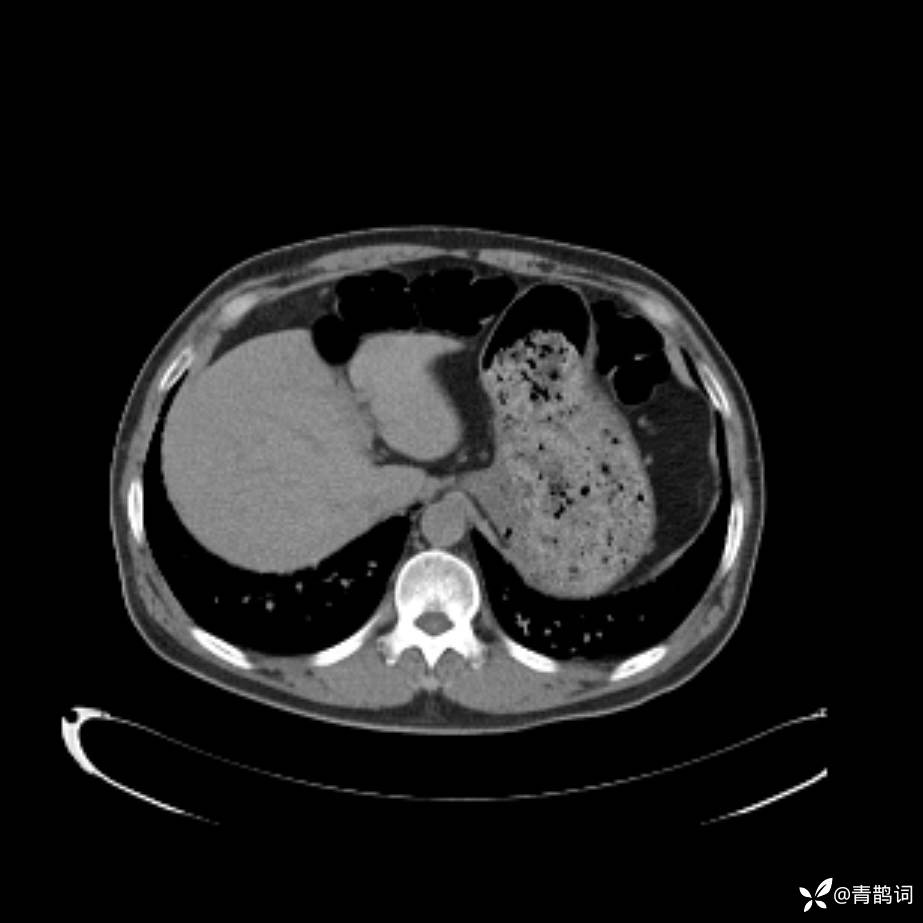

患者年龄:30岁。

患者性别:男。

简要病史:左颜面部肿胀2年,反复咳嗽咳痰,逐渐加重。

结合病史及影像学表现,期待评论区各位老师各抒己见~